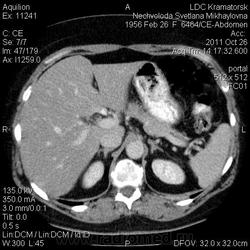

Здравствуйте! Вот уже месяц не могут поставить диагноз. Первичный очаг найти не удалось. Множественная миелома (несекретирующая?, т.к. по крови стерн. пункция не дает результата)?

Была взята биопсия с пораженного позвонка, но в материале оказалось мало клеток кости, наличие фиброзных клеток. Материал трепанбиопсии правой подвздошной так же содержал мало клеток, т.к. удалось углубиться всего лишь на 7мм (дальше сломалась игла, по словам врача скорее всего об фиброзное образ.). Можно ли по результатам КТ предложить повторный, более прицельный поиск? Что еще говорит КТ?

По имеющимся файлам-дайком я не нашла признаков опухоли. Имеется множественное остеолитическое поражение позвоночника, ребер, грудины, частично - таза. Лимфоузлы не увеличены. Тоже поставила бы на первое место миеломную болезнь. Диагностирование её не всегда простое дело. Поражена грудина и, наверное, нужно посоветоваться с онкологом (гематологом) стоит ли сделать стернальную пункцию.Советую написать в личку tatyana.

Думаю тоже в первую очередь здесь миеломная болезнь, процентов на 80%. Но результаты лабораторных анализов действительно неоднозначные.

Повторюсь: по имеющимся данным наиболее вероятной считаю миеломную болезнь